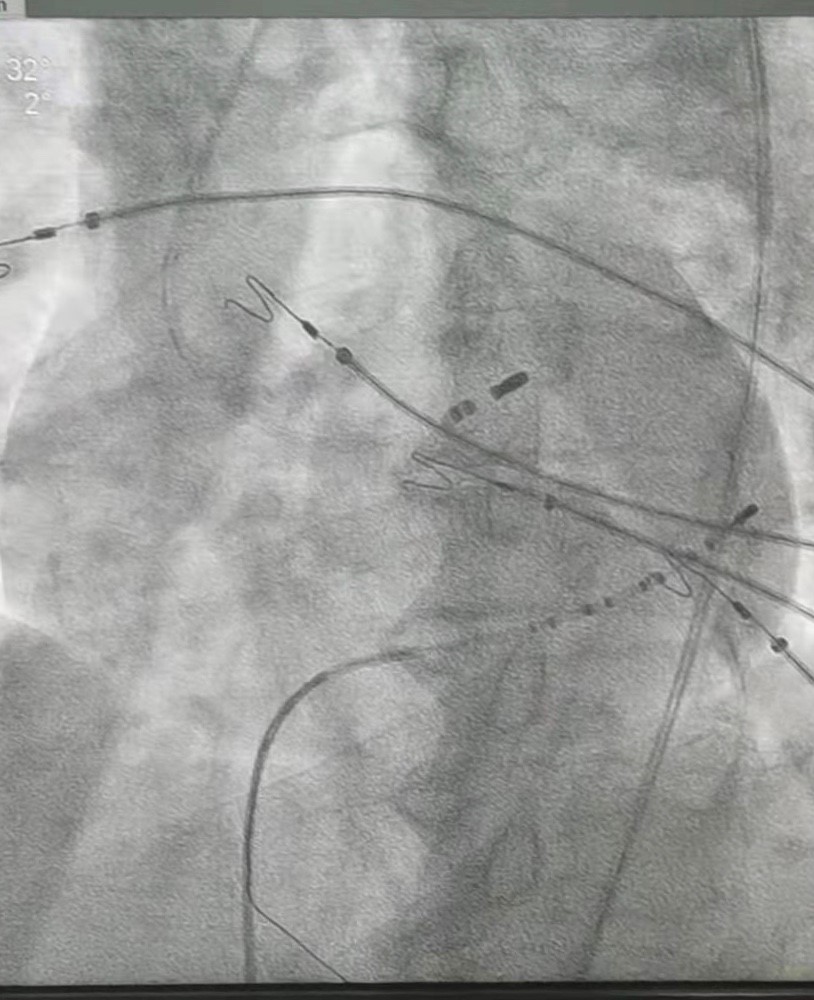

此次接受治疗的两位患者,一例患者为老年男性,动态心电图提示早博共有8万余次;另一例患者是一名中年女性,长期口服抗心律失常药物,动态心电图扔提示早搏1.8万余次。两位患者在我院心内三科负责人郑崔成和梁羽医生共同实施经导管射频消融术后,动态心电图提示室性早搏0次,彻底治愈了困扰患者的顽疾,患者和家属亲自送上锦旗表示感谢:“市医院心内三科团队解决了我们的“心”病,简直太神奇了”。

据梁羽医生介绍,经管射频消融术是一种微创的治疗方法,是将特制的导管送到患者心脏,找到引起室早的“病灶”(起源点,往往就几毫米大小),发放射频电流,将“病灶”消除或改良,从而起到根治室早或使室早明显减少的作用。具有不开刀、不缝线、创伤小、恢复快的优点,治疗成功后患者不仅可以免受反复发作症状的困扰,而且还能避免快速心率对心脏结构与功能的不良影响以及长期抗心律失常药物的毒副作用。